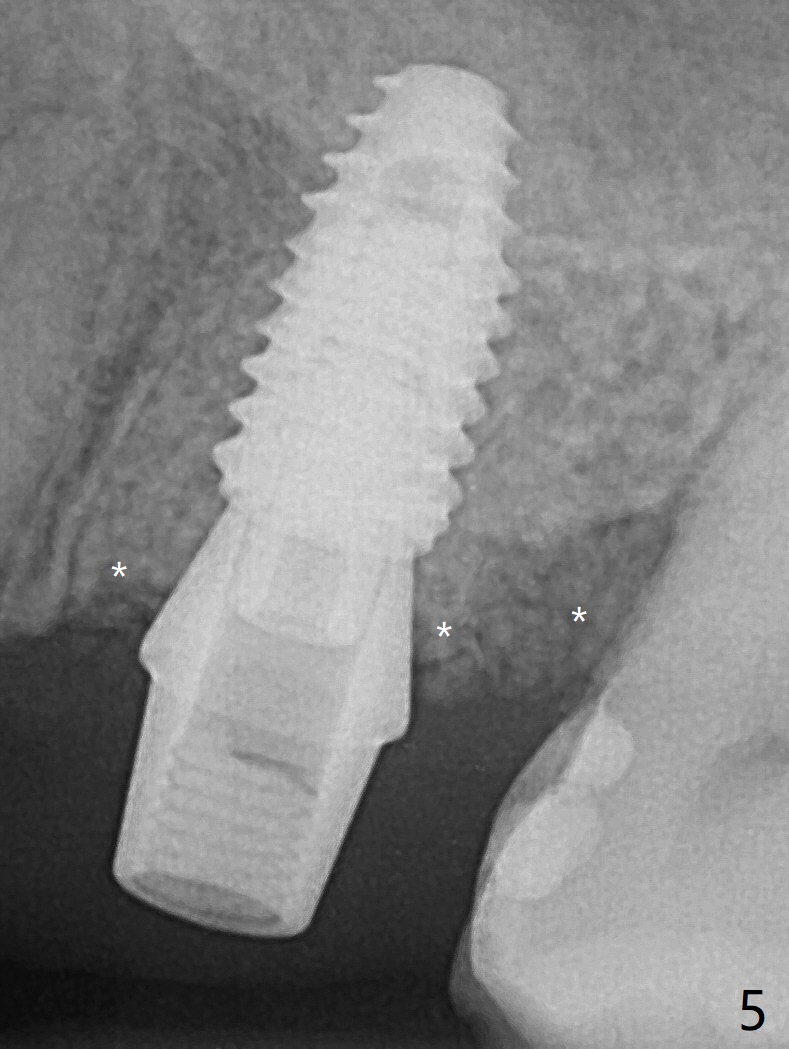

虽然没有保留左上6牙根,但是导板好像帮助钻洞(O)正好位于中隔当中(图一,二)。使用4.5(不是4.0)x10毫米钻头后,粘性骨粉和报废植体完成上颌窦提升术(图三:S)。拔除第一磨牙后发现第二磨牙近中面龋齿,立刻进行保守修补(图三:箭头);两个磨牙之间还有骨质吸收(*)。放置正式植体(10Ncm)后(图四),三个牙槽窝填入骨粉,包括近中颊侧(MB)和远中颊侧(DB),这时磨牙间缺损初步填补(*),然后放置基台以及基台周围骨粉,进一步充填磨牙间缺失(图五:*)。术后临时牙冠脱落两次,病人自己放回去,术后一周取出牙冠,骨粉还在(图六),腭侧有单纯疱疹病变(图七:>),开抗病毒漱口水处方,然后使用临时粘固粉。术后7个月15号牙近中牙槽嵴增高大约1.4毫米(图八:空箭头,从近中最颈部树脂算起)。术后七个月临时牙冠一直使用,防止食物坎塞,有利于骨质再生。术后7个月基台在口内没有更动(术中手拧紧),牙冠口内粘固,少量粘固剂遗留(图八:^)。牙冠/基台取出,去除粘固剂,牙冠/基台就位,用扳手拧紧(30 Ncm),基台与植体仍保持完全接触(图九)。只要植体植入角度好,没有倒凹,牙冠/基台再次就位就没有问题。